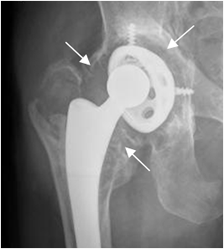

A: Rx AP. Aumento de la lucencia periprotésica, que indica aflojamiento. (Flechas delgadas).

B: TAC reconstrucción coronal en ventana de hueso y C: TAC reconstrucción coronal en ventana de tejido. Adicionalmente hay zona de osteolisis en el trocánter mayor (Flecha gruesa) y otra lesión osteolítica en el ramo isquiopúbico. (Cabeza de flecha).